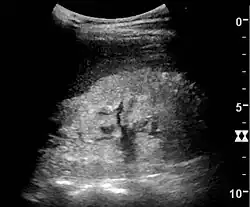

Complex cysts can have membranes dividing the fluid-filled center with internal echoes, calcifications or irregular thickened walls. The complex cyst can be further evaluated with Doppler US, and for Bosniak classification and follow-up of complex cysts, either contrast-enhanced ultrasound (CEUS) or contrast CT is used (Figure 6). The Bosniak classification is divided into four groups going from I, corresponding to a simple cyst, to IV, corresponding to a cyst with solid parts and an 85–100% risk of malignancy.[1] In polycystic kidney disease, multiple cysts of varying size in close contact with each other are seen filling virtually the entire renal region. In advanced stages of this disease, the kidneys are enlarged with a lack of corticomedullary differentiation (Figure 7).[1]